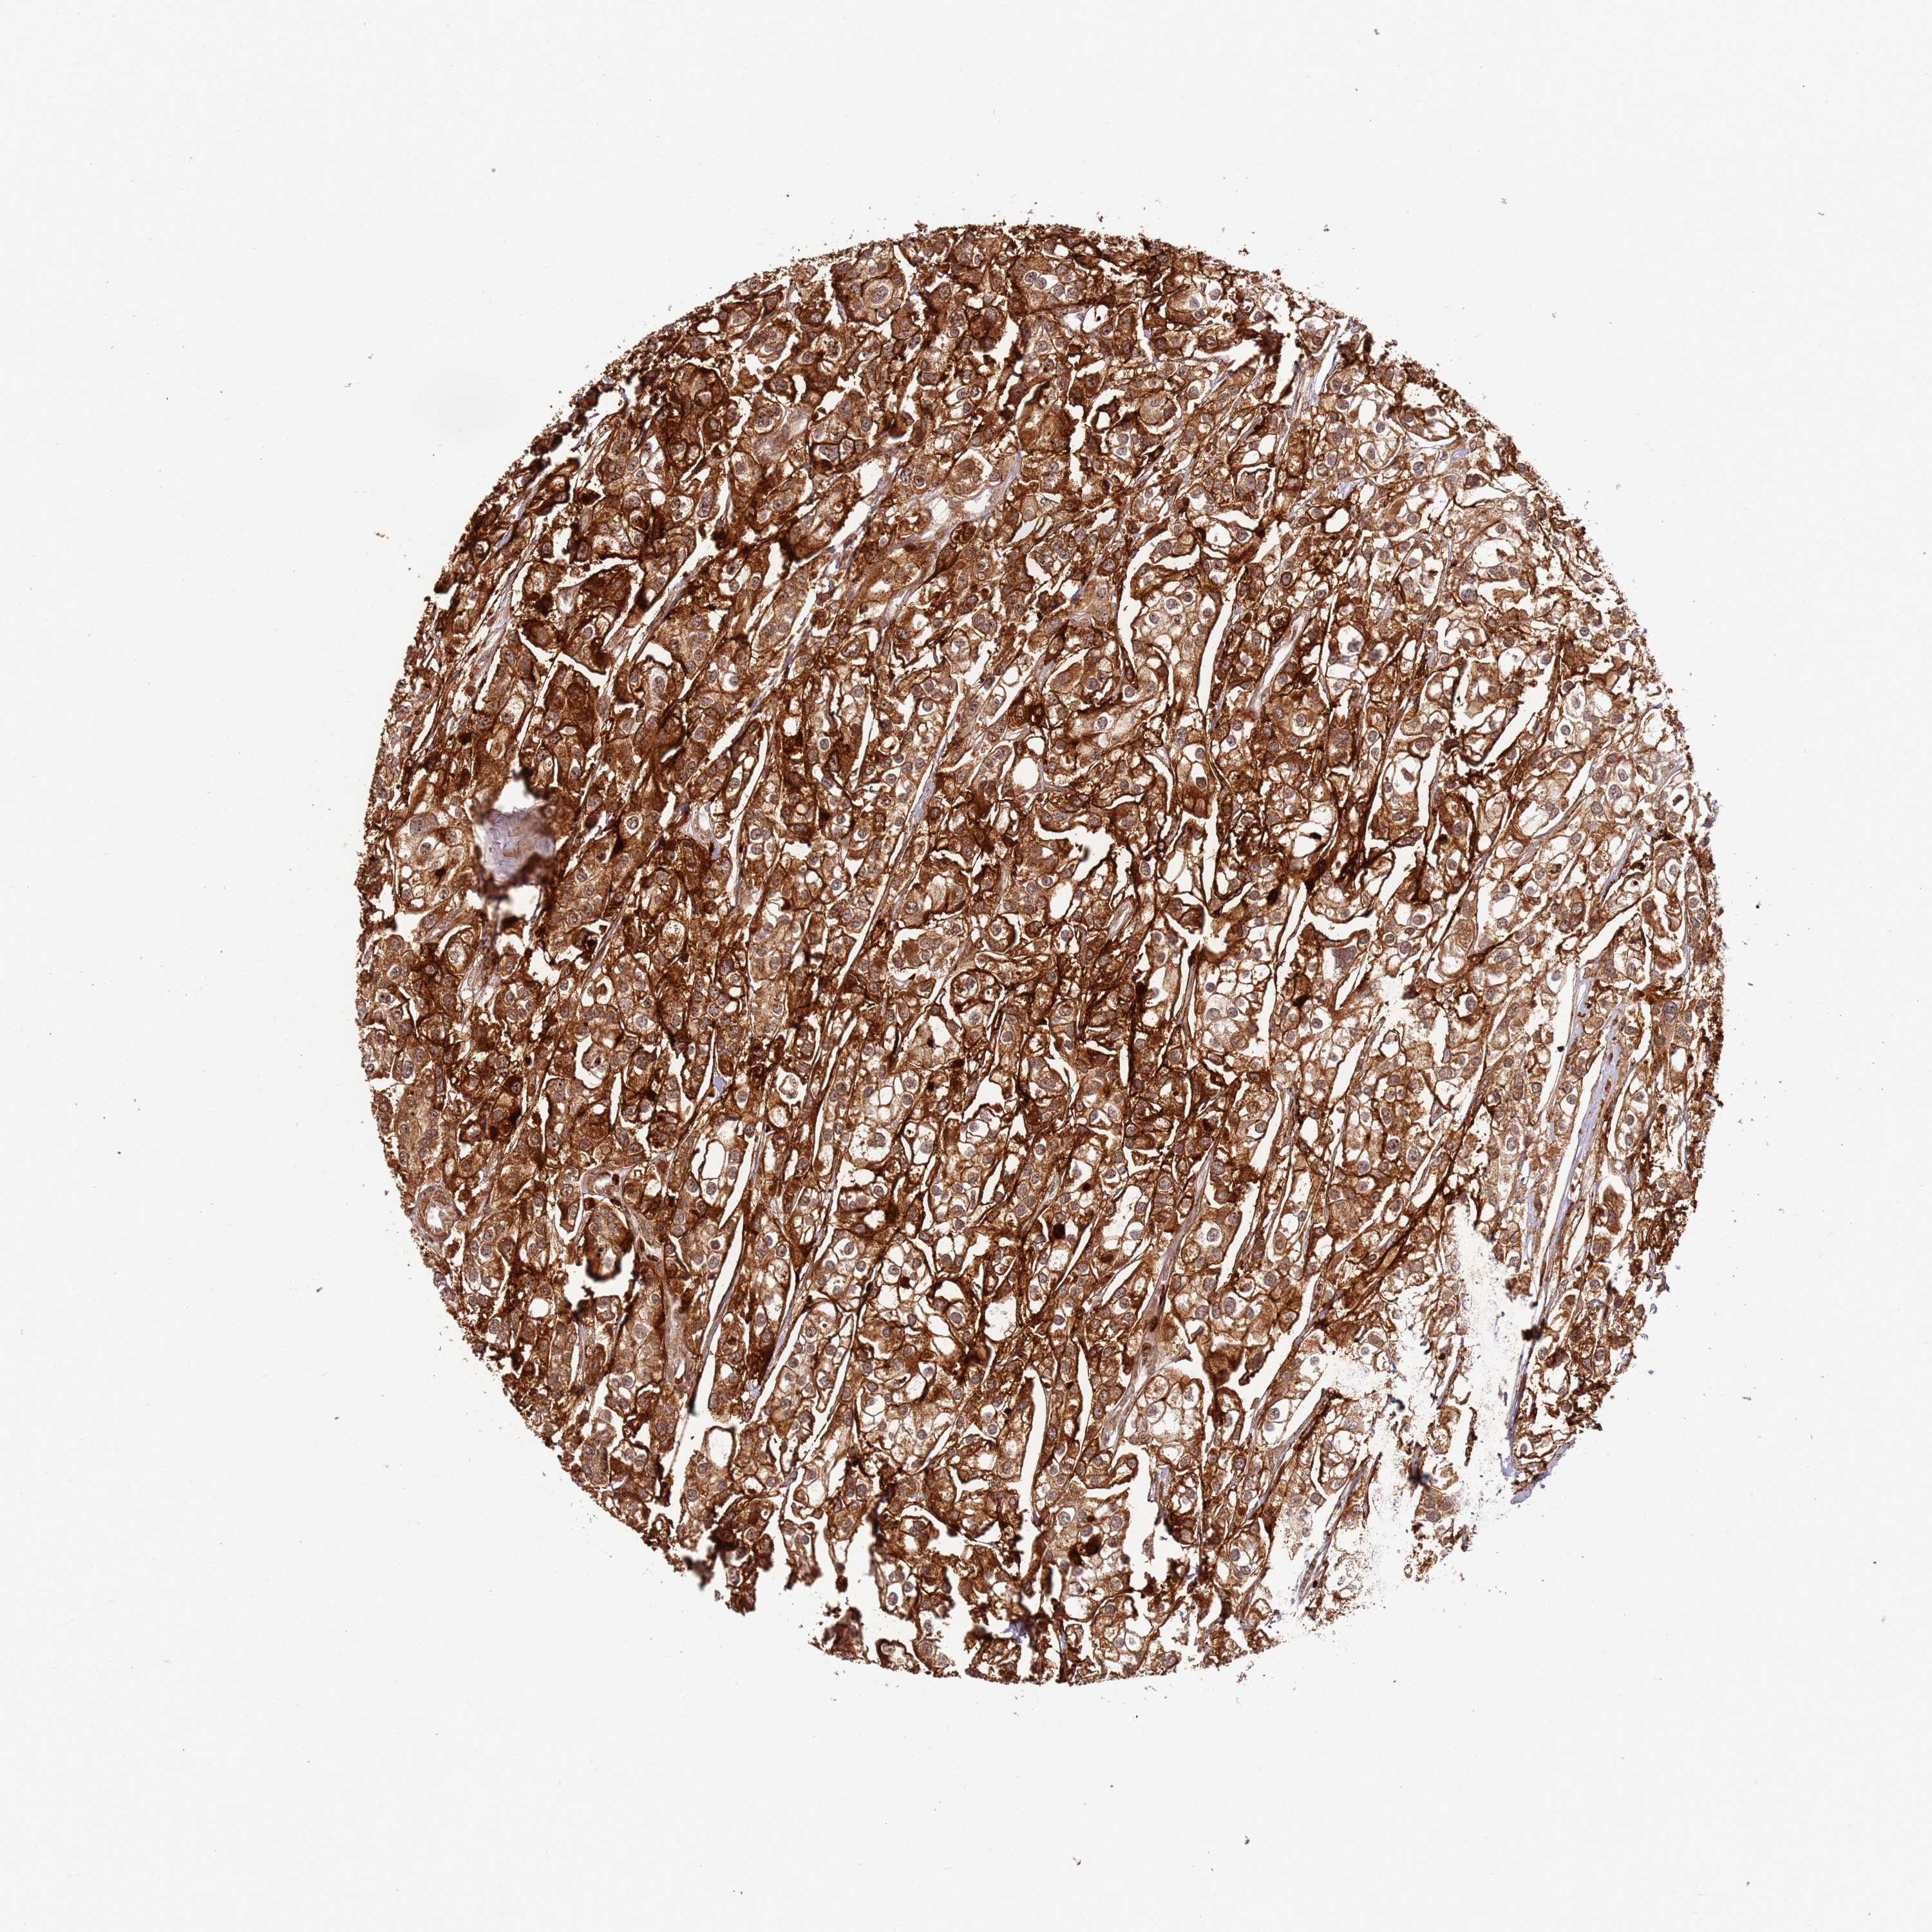

UROTHELIAL CANCER - Protein expressioni

A mouse-over function shows sample information and annotation data. Click on an image to view it in a full screen mode. Samples can be filtered based on level of antibody staining by selecting one or several of the following categories: high, medium, low and not detected. The assay and annotation is described here.

Note that samples used for immunohistochemistry by the Human Protein Atlas do not correspond to samples in the TCGA dataset.

Antibody stainingi

Antibody staining in the annotated cell types in the current human tissue is reported as not detected, low, medium, or high, based on conventional immunohistochemistry profiling in selected tissues. This score is based on the combination of the staining intensity and fraction of stained cells.

Each image is clickable and will lead to virtual microscopy that enables deeper exploration of all samples and also displays staining intensity scores, fraction scores and subcellular localization as well as patient and tissue information for each sample.

Antibody HPA047506

Staining

High

Medium

Low

Not detected

Intensity

Strong

Moderate

Weak

Negative

Quantity

>75%

75%-25%

<25%

None

Location

Nuclear

Cytoplasmic/membranous

Cytoplasmic/membranous,nuclear

Urothelial carcinoma, High grade

Urothelial carcinoma, Low grade